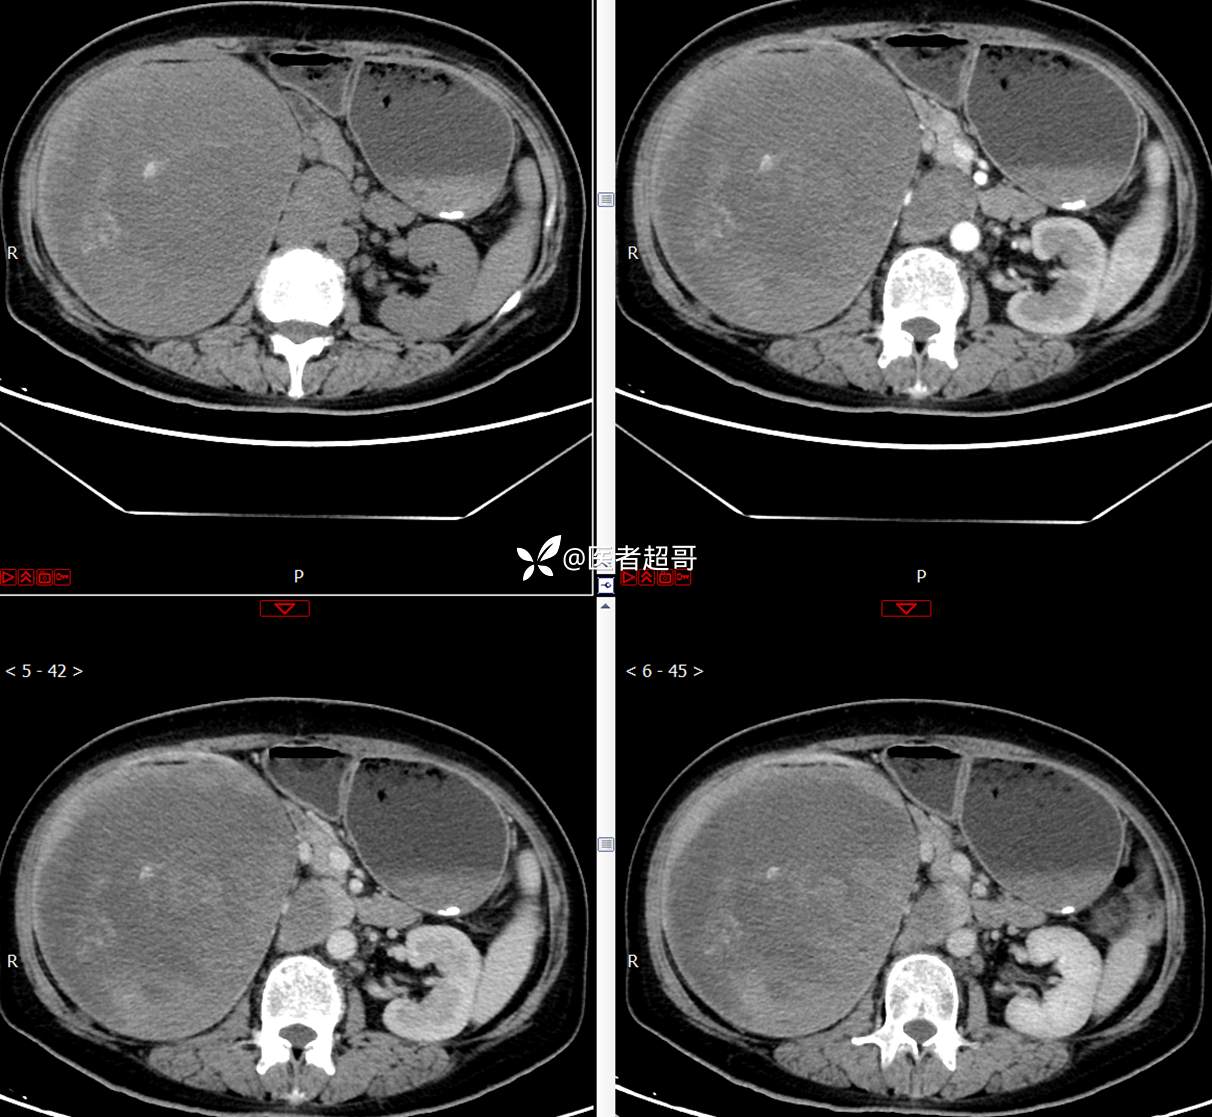

【影诊笔记743】腹腔肿物?腹膜后肿物?请先定位,后定性!有病理!

主 诉:发现右上腹肿物1周余。

现病史:患者1周余前发现右上腹有一半球形巨大肿物,约18cm*15cm大小,既往贫血病史3年余,诉乏力,易疲劳,偶有头晕,活动后心悸,无腹痛、腹胀,无恶心、呕吐,无尿频、尿急、尿痛,无排尿困难,患者为求进一步治疗,来我院消化内科就诊,门诊行肝.胆.胰.脾.肾彩超示:右肾上部囊实性占位,范围约18.0cm×11.7cm×16.4cm,边界清,形态规则,建议进一步检查,腹膜后实性结节。我科遂以“肾肿物”收治入院,患者自发病以来,神志清、精神可,睡眠、饮食可,二便正常,体重、体力略有下降。